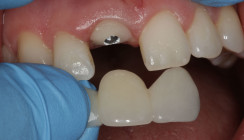

Neben patientenbezogenen und chirurgischen Faktoren spielt dabei auch das Implantatdesign eine wesentliche Rolle. Die vorliegende Falldokumentation zeigt eine Sofortimplantation Regio 11 mit digitaler Planung anhand von DICOM- und STL-Daten. Die präoperative Planung erfolgte softwaregestützt, die Implantatposition wurde prothetisch orientiert festgelegt. Klinisch und radiologisch lagen günstige Ausgangsbedingungen für eine Sofortimplantation mit Sofortversorgung vor.

Zur Erreichung einer hohen Primärstabilität wurde ein Implantat mit aggressivem Gewinde bei einem Außendurchmesser von 3,5 mm und einem Kerndurchmesser von ca. 2,8 mm eingesetzt. Ergänzend erfolgte eine unterpräparierte Bohrung. Solche Kombinationen aus Gewindedesign, Implantatgeometrie und Bohrprotokoll sind in der klinischen Praxis etabliert, erfordern jedoch eine sorgfältige Risikoabschätzung hinsichtlich der mechanischen Belastung des Implantatkörpers.